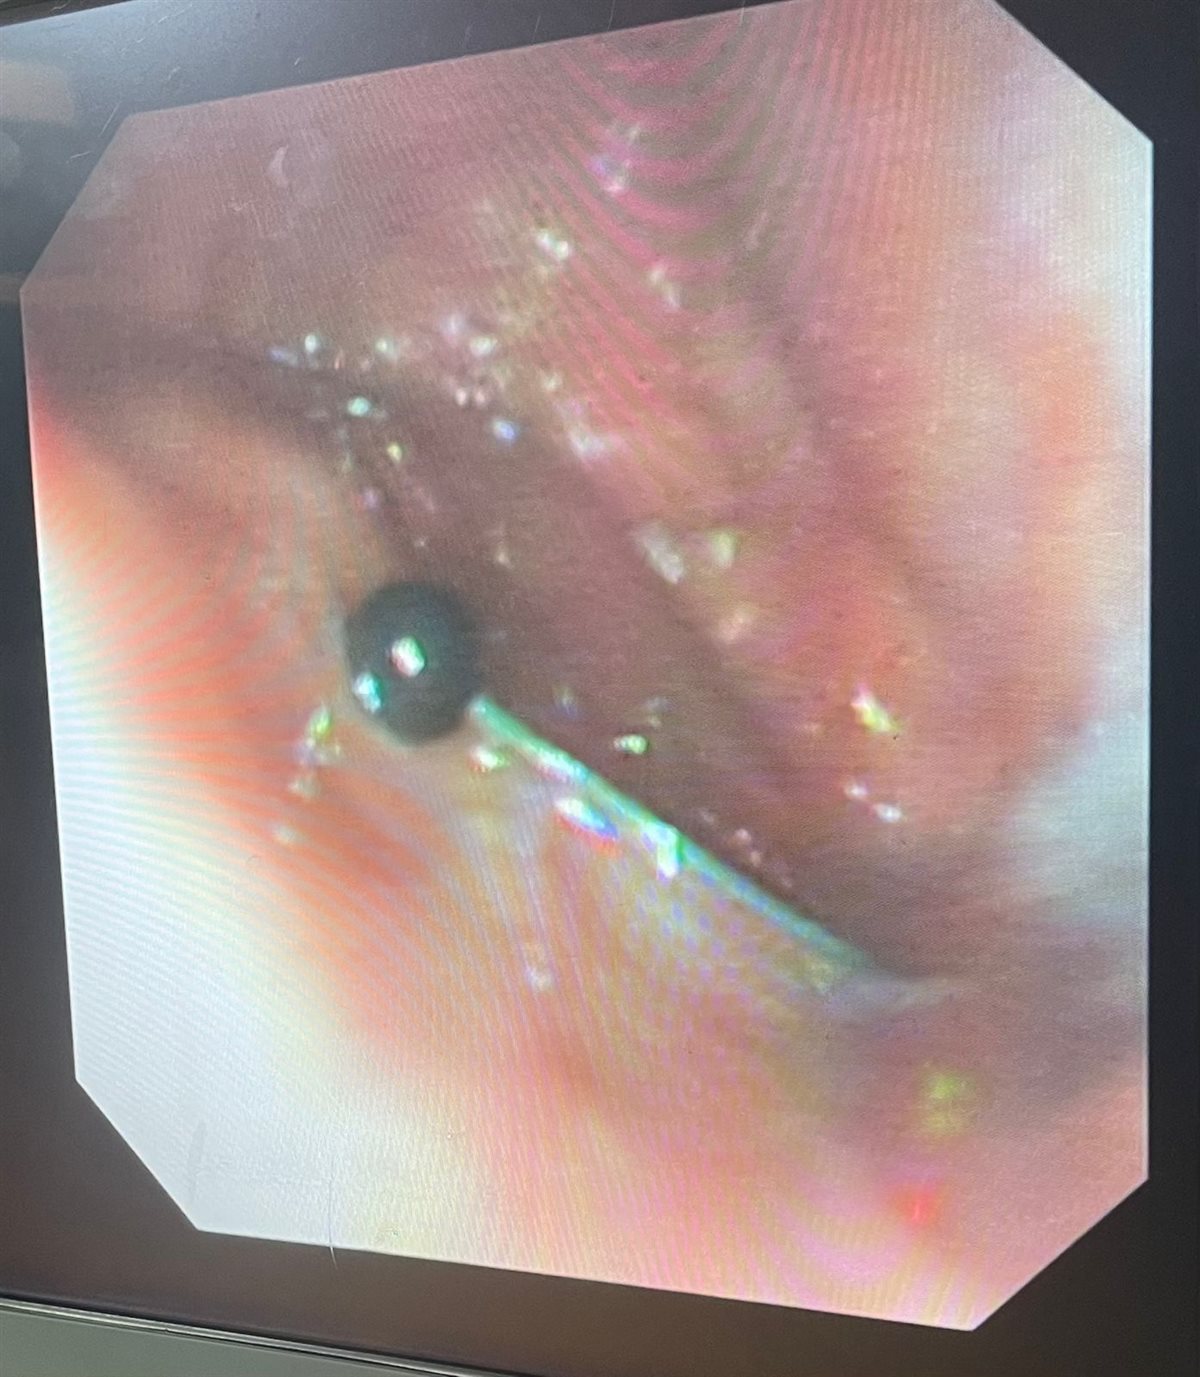

نجح فريق طبي من وحدة أمراض الجهاز الهضمي والكبد ومناظير الأطفال بقسم طب الأطفال بمستشفى سوهاج الجامعي في إجراء تدخل دقيق لاستخراج دبوس من معدة صغير يبلغ من العمر 4 سنوات، باستخدام منظار معدة خاص بالأطفال، دون حدوث أي مضاعفات، وغادر الطفل المستشفى بعد ثلاث ساعات فقط من الإجراء، وهو في حالة صحية جيدة.

وأكد الدكتور أحمد كمال، المدير التنفيذي للمستشفيات الجامعية، أن التعامل مع الحالة تم بسرعة وكفاءة، حيث تمكن الفريق الطبي من استخدام المنظار الخاص بالأطفال لاستخراج الدبوس دون أي تدخل جراحي، مما ساهم في خروج الطفل من المستشفى في نفس اليوم بحالة ممتازة.